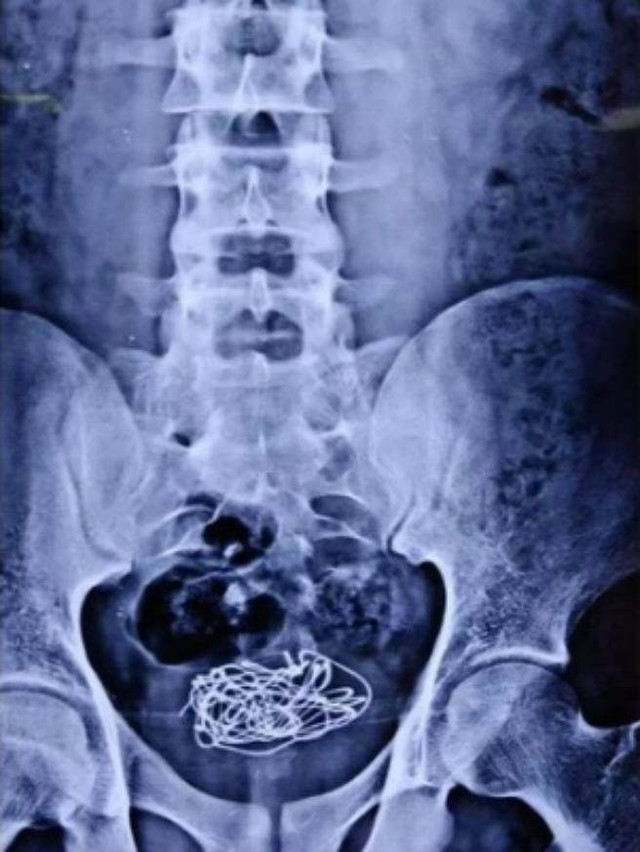

Đúng như dự đoán, trong lúc chụp X-quang, các bác sĩ phát hiện, chàng trai trẻ đã nhét dị vật vào trong cơ thể mình. Cụ thể, trong bàng quang của thanh niên này có một đoạn dây điện. Đoạn dây điện này cũng chính là nguyên nhân khiến cậu bị đau bụng dữ dội, không thuốc nào chữa được.

Cuối cùng, biết không thể giấu được nữa, chàng trai trẻ đã thừa nhận tất cả. Cậu cho biết, khoảng 10 ngày trước, trong lúc tự thỏa mãn nhu cầu sinh lý, để kích thích hơn, cậu đã nhét một đoạn dây điện từ ngoài vào niệu đạo. Không ngờ rằng lúc nhét vào thì được, lúc lấy ra thì không thể, dẫn đến chuyện đi tiểu cũng đau đớn, khó chịu, tiếp đó là đau bụng dữ dội.